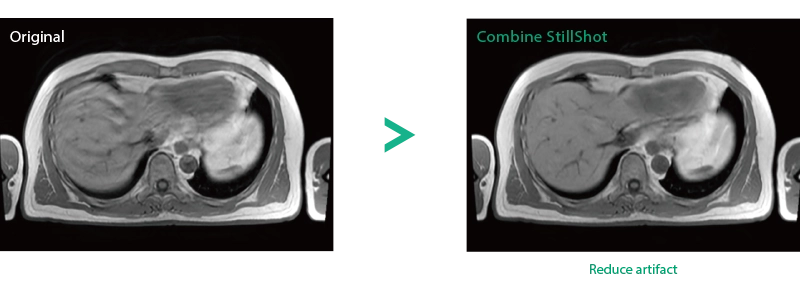

Imperfect imaging data to be better image quality through post-processing

By providing functions to remove and suppress artifacts in the imaging data and to generate reconstructed images from limited imaging data, it reduces the re-imaging rate and supports the realization of smooth MRI examinations.

Reduce artifacts caused by patient movement, such as coughing or sneezing, by post reconstruction.

Improving SNR and reducing wrap-around artifact through post reconstruction.

When motion artifacts occurs in the image due to coughing, sneezing, or involuntary movements, either or both the visual information acquired by monitoring cameras, Synergy Vision, and the intrabody information acquired by the navigator pulse can be used to provide an image with reduced artifacts. This reduces the re-imaging rate.

Body movements that affect image quality are detected from monitoring cameras based on thresholds derived for each body part.

Movements within the body are detected by navigator pulses. Body movements that significantly affect image quality are detected based on the error between pulses.

Deep Learning technology*8 enables image quality adjustment after imaging is complete. It optimize SNR and improve image sharpness by processing MRI signals in stages (k-space signal processing). This brings super-resolution and reduces truncation artifacts.

When the size in the phase encoding direction is incorrectly set , the signal outside the FOV will fold back and appear as artifacts in the image. Exp. RAPID reconstructs the image according to the specified FOV magnification ratio. Artifacts can be removed in post-processing.